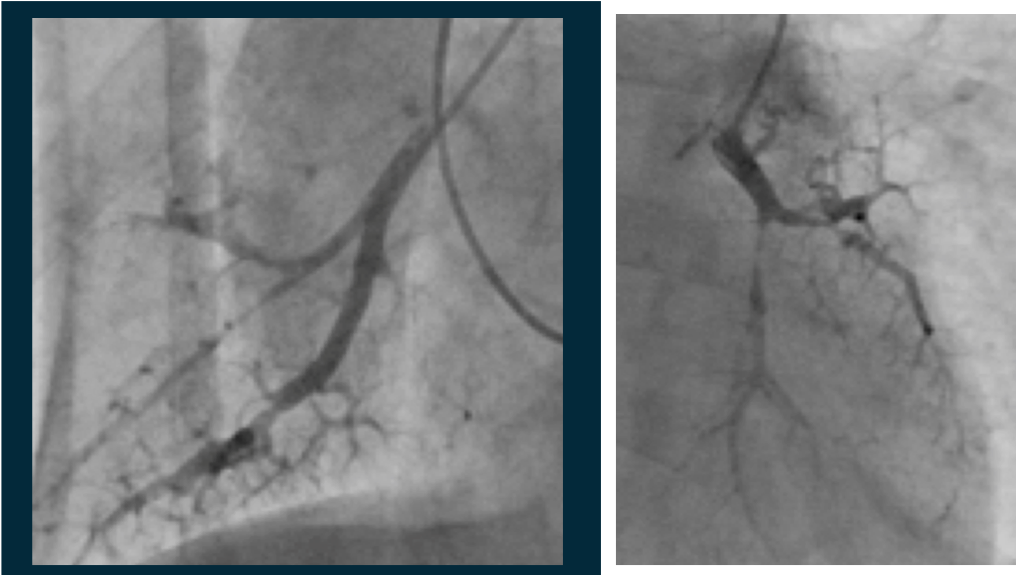

症例2:図4 肺動脈造影(PAG)所見

出典

img

1: 著者提供